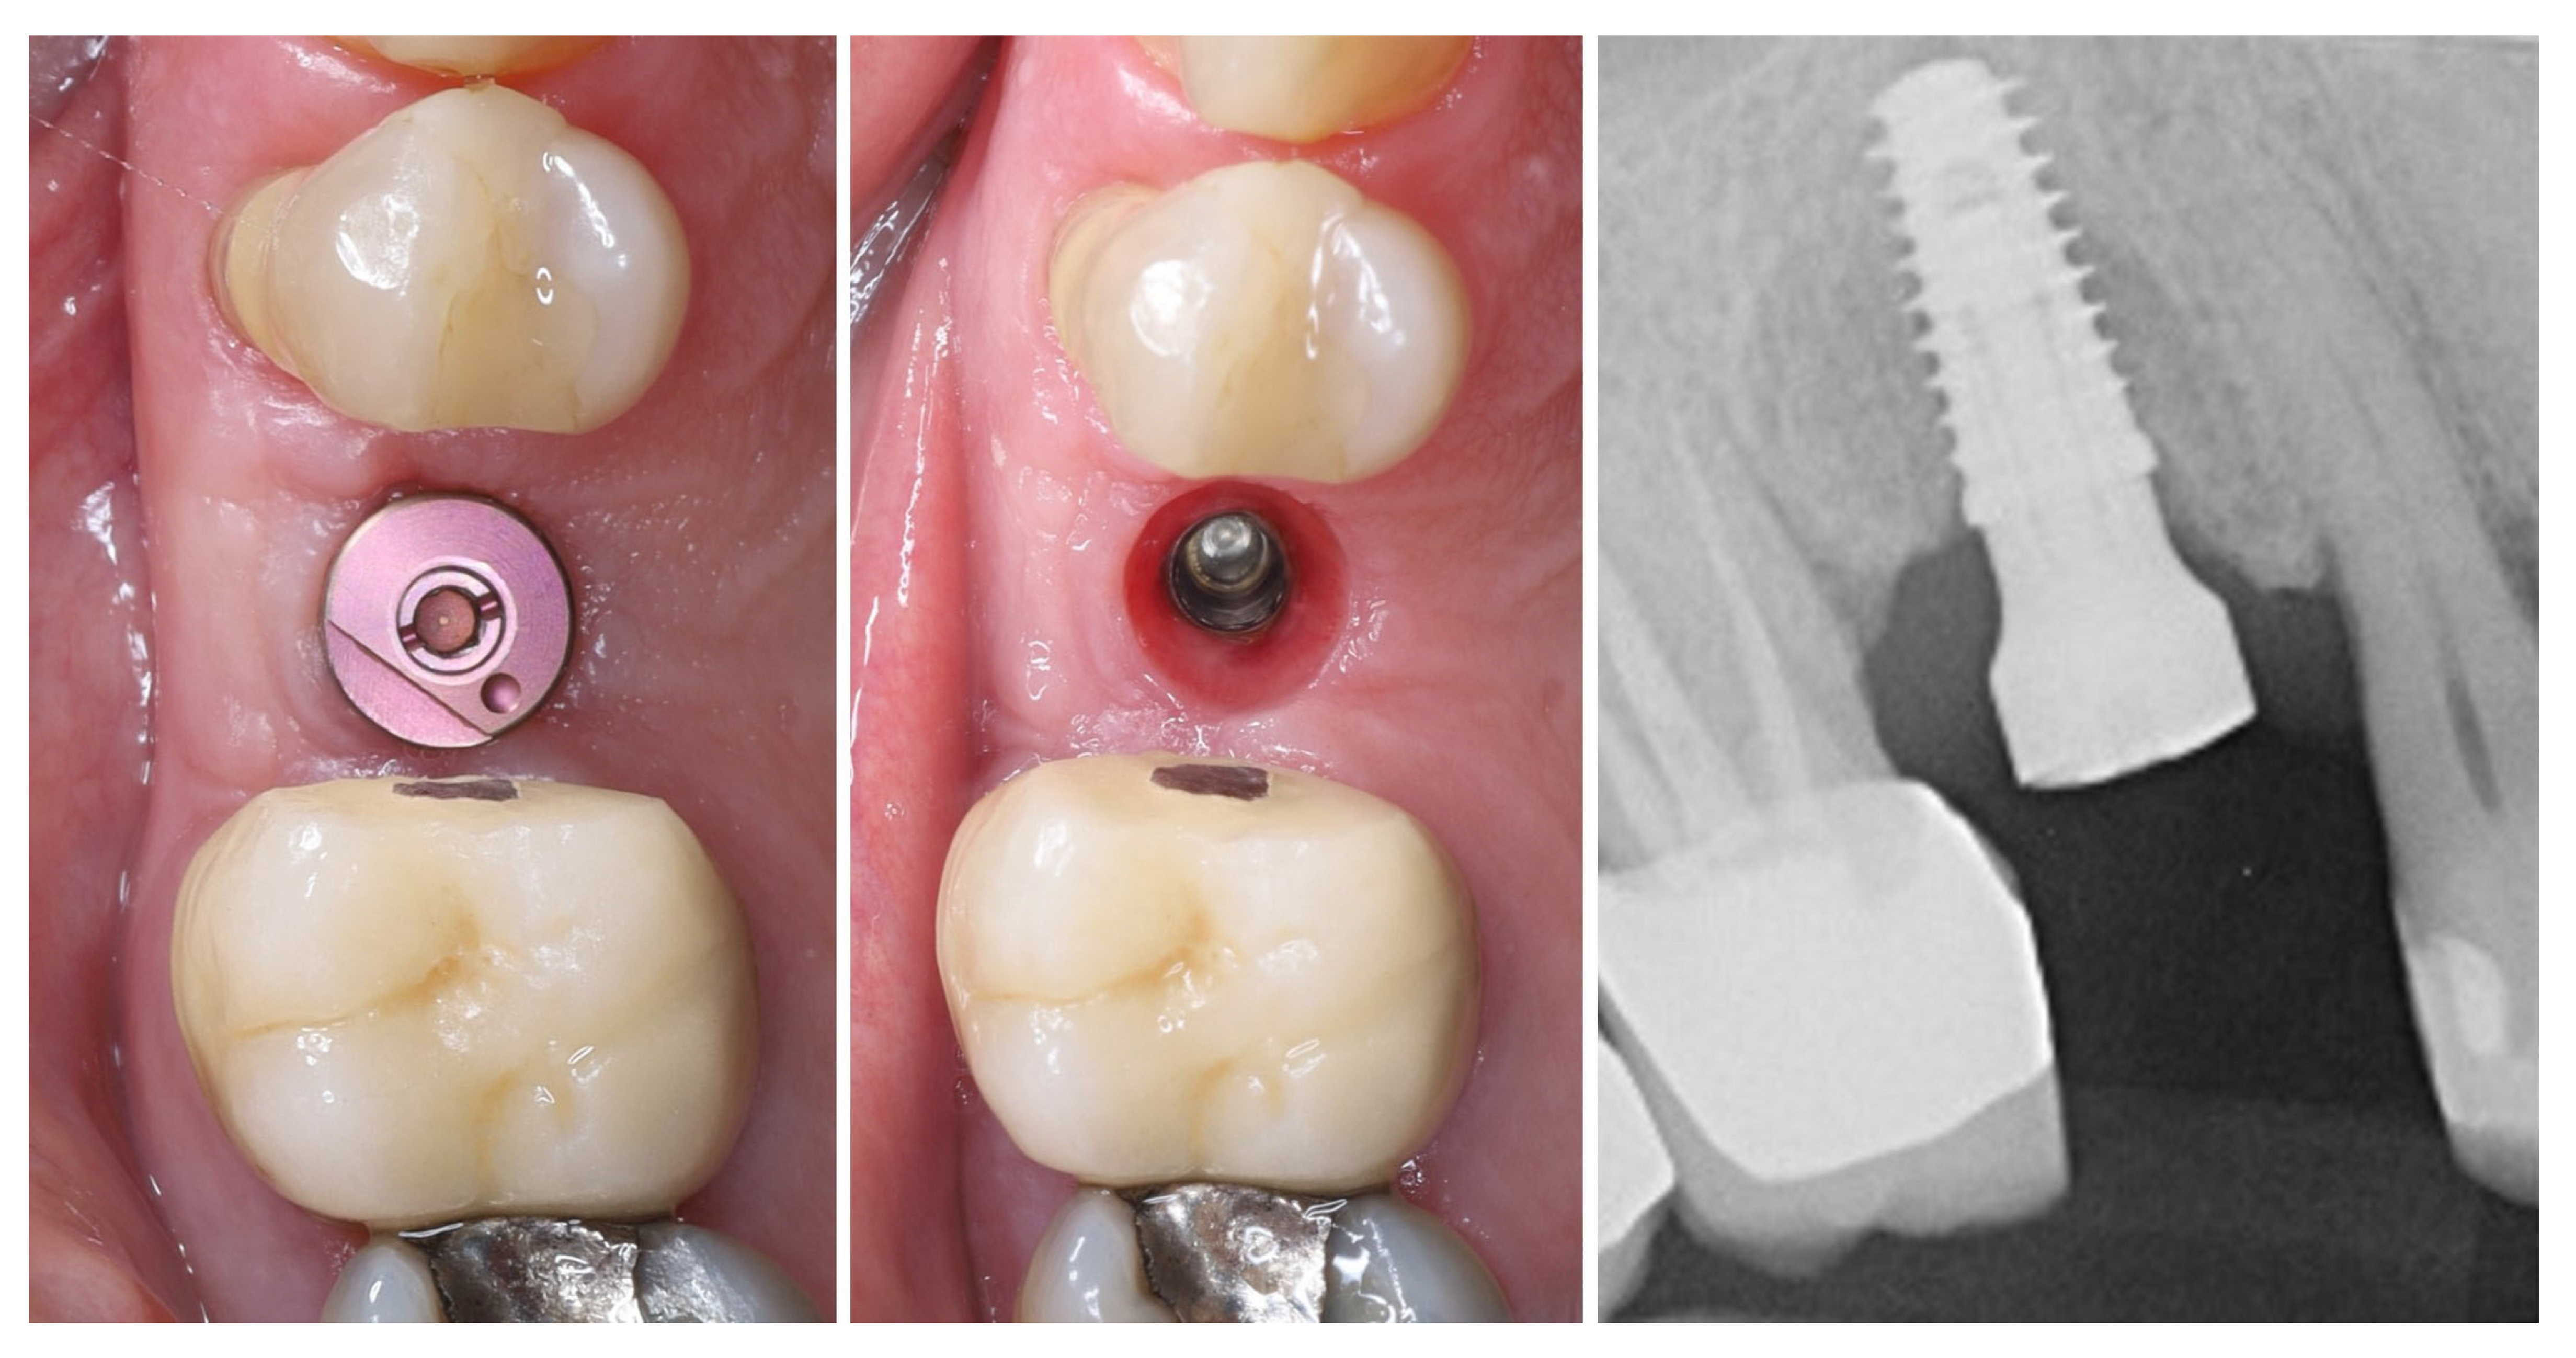

The implant was placed using a digitally designed surgical guide to ensure prosthetically driven positioning. Intraoperative images demonstrate the sequence of guided placement: preparation of the osteotomy through the guide with visualization of the prepared site (left), dental implant (T3Pro, ZimVie Inc., Palm Beach Gardens, FL, USA) before placement (middle), and final implant insertion (right) with insertion torque ~50N/cm. The use of a surgical template allowed precise three-dimensional implant placement, optimal angulation, and preservation of surrounding soft and hard tissues (Figure 8).

Figure 8.

Guided implantation protocol.

The selected implant was positioned in the prosthetically driven position, with appropriate bone thickness at the buccal aspect and surrounded by healthy soft tissues (left). Another advantage of this surgical approach is the possibility to adapt the implant insertion depth corresponding to the soft tissue thickness in order to provide enough soft tissue thickness to enhance the stability of the peri-implant bone. The intraoperative measurements confirmed excellent primary stability, with ISQ values of 82 bucco-lingually and 85 mesio-distally (right). These parameters indicated optimal mechanical anchorage of the fixture within the alveolar bone, ensuring favourable conditions for osseointegration (Figure 9).

Figure 9.

Implant placement and initial stability.

A multi-purpose healing abutment, serving also as a scan body (encode abutment ZimVie Inc., Palm Beach Gardens, FL, USA), was connected, providing proper concave emergence profile in the critical contour zone of the transmucosal area. The de-epithelized crestal flap was rolled and fixated to the inner surface of the buccal flap with a horizontal mattress suture (7/0 PGA). The buccal flap was fixed to the “anatomical” part of the peri-implant papillae (6/0 PGA). The buccal positioning of the rolled connective tissue creates a thickened gingival margin, intended to improve peri-implant soft tissue stability and long-term esthetic outcomes. The surgical site shows adequate adaptation of the flap margins around the healing abutment, enhancing the primary healing, thus reflecting proper flap management and atraumatic technique. The 2D X-ray performed after implant placement shows a proper implant position corresponding to the morphology of the alveolar crest (Figure 10).

Figure 10.

Clinical and X-ray view after implant placement and roll flap adaptation.

Figure 11 illustrates the peri-implant soft tissue condition 14 days after simultaneous implant placement and roll flap augmentation at suture removal. The buccal flap shows uneventful healing with adequate tissue thickness and favourable contouring around the healing abutment. The mucosal margin appears stable, with absence of dehiscence or inflammation, indicating successful integration of the rolled flap. Different views demonstrate proper adaptation of the peri-implant mucosa, confirming the effectiveness of the roll flap in enhancing buccal soft tissue thickness and achieving a harmonious gingival architecture.

Figure 11.

Clinical views before and after suture removal (14 days post-op).

Three months postoperatively, the peri-implant site demonstrates complete mucosal healing with stable, well-contoured soft tissues. The healing abutment is visible in situ (left), with healthy, keratinized mucosa surrounding the transmucosal interface. Following removal of the healing abutment (middle), the implant platform shows a mature and stable soft tissue collar without signs of inflammation, recession, or dehiscence. The X-ray control reveals stable crestal bone levels without signs of bone remodelling (right) (Figure 12). The roll flap augmentation resulted in increased buccal tissue thickness and harmonious gingival architecture, providing favourable conditions for prosthetic restoration.

Figure 12.

Mature peri-implant mucosa and stable crestal bone after roll flap augmentation (3 months post-op).